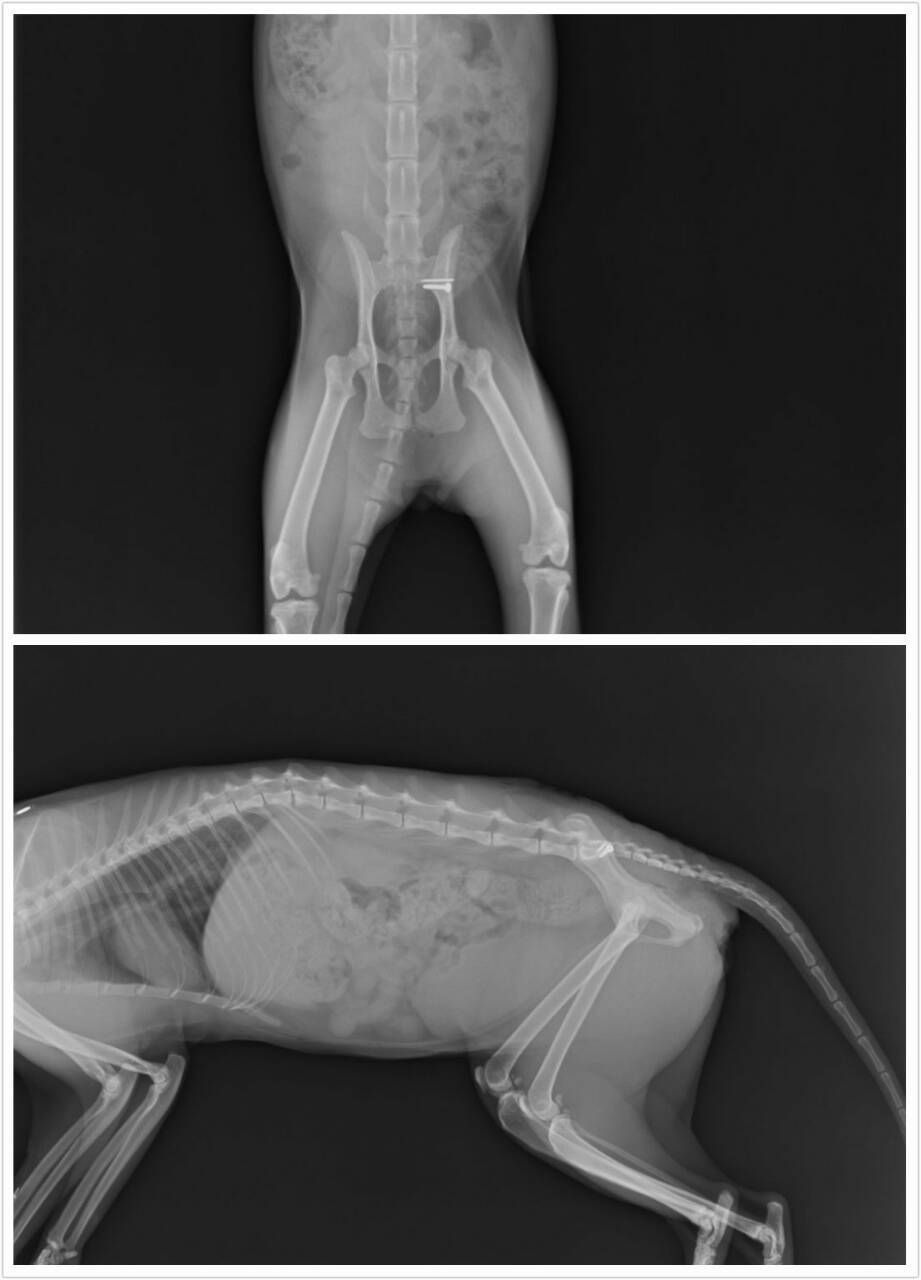

小刀後來傷口末端的縫線有點開,傷口有滲出液,越來越嚴重,醫生原本以為是他一直去磨籠子導致,所以就想說幫他清創一下傷口再縫合,結果傷口一打開不得了,裡面組織都發炎還有點潰爛,一直清下去竟然發現有骨釘跟螺絲…於是醫生盡量把一些爛肉跟不好的組織清掉,然後縫合,後來拍x光發現應該是左側腸薦關節有打骨釘跟螺絲,這讓醫生有點傻眼,因為來的時候原本壽山收容所給的資料只是外傷,所以看起來外面傷口好好的醫生就只給一些簡單的消炎藥,結果竟然是有動骨科,而且傷口現在又有問題,,後續的狀況目前無法評估,有可能傷口會持續潰爛,也有可能發炎控制住慢慢就會好,醫生先幫他上留置針,打靜脈抗生素,傷口包紮,靜待接下來的變化……

清創手術完, 上留置針打靜脈的抗生素,醫生持續治療,為了讓貓咪進一步受更多治療,目前貓咪轉院繼續治療,謝謝大家幫助這癱瘓背傷的可憐貓咪,感恩^^